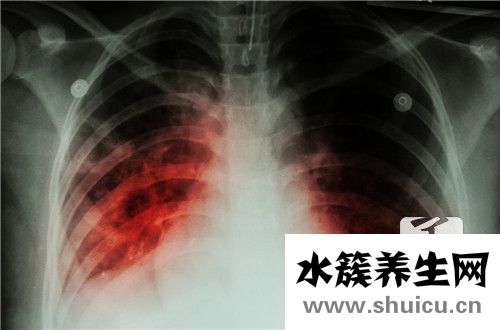

?由于霧霾更加嚴重并且肺癌的患病率仍然很高,因此人們非常重視肺部的健康。 每年,身體檢查中心都要檢查肺部。 可能發(fā)現有些人有肺結節(jié)。 由于肺部在體內,因此當結節(jié)出現時,很難及時找到它們,并且它們...